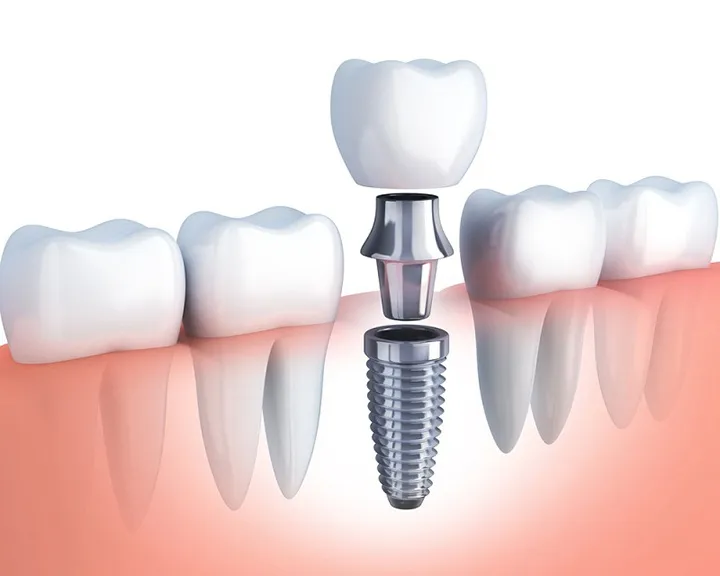

Sau khi nhổ răng, bạn cần phục hồi chức năng ăn nhai và thẩm mỹ của hàm răng. Vì thế bệnh nhân có thể lựa chọn phương pháp cấy ghép Implant. Implant không chỉ giúp thay thế răng mất một cách hiệu quả. Nó còn duy trì sự ổn định lâu dài cho sức khỏe răng miệng. Đồng thời đem lại vẻ đẹp tự nhiên cho nụ cười.